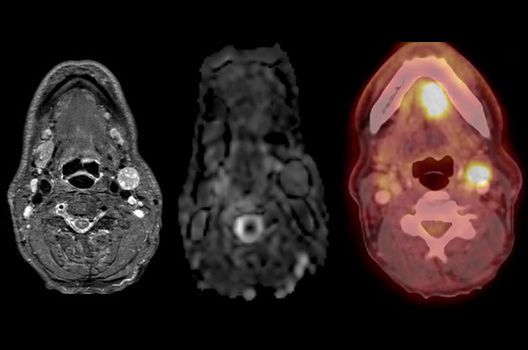

Onkologische und Hybridbildgebung

- PET/MRT in der Neuroonkologie

- Diffusion Kurtosis Imaging

- Molekulare Bildgebung mit innovativen Tracern in Kooperation mit der Nuklearmedizin und Radiopharmazie

Die Hybridbildgebung mittels PET/MRT spielt insbesondere in der onkologischen Bildgebung eine wichtige Rolle. Eine mögliche Fragestellung ist die Unterscheidung zwischen einem Tumorrezidiv oder therapeutisch assoziierten Veränderungen insbesondere dann, wenn diese Frage mittels MRT alleine nicht beantwortet werden kann.

Die bildgebende Diagnostik und Verlaufsbeurteilung von Tumoren des Nervensystems ist einer der klinischen und Forschungsschwerpunkte unserer Abteilung. Eine besondere Bedeutung kommt der Hybrid-Bildgebung zu. Das Universitätsklinikum verfügt über einen integrierten Ganzkörper-PET/MRT-Scanner, der die Vorteile der MRT-Bildgebung und der Positronenemissionstherapie (PET) vereinigt. Aufgrund der langjährigen klinischen Arbeit und Forschungstätigkeit mit diesem Gerät hat die Neuroradiologie Tübingen maßgeblich zur Etablierung dieses Verfahrens beigetragen. Auch weiterhin forschen wir intensiv an neuen Methoden zur frühen Einordnung von Tumoren und insbesondere Tumorrezidiven, die mit anderen Methoden häufig nicht erfasst werden können.